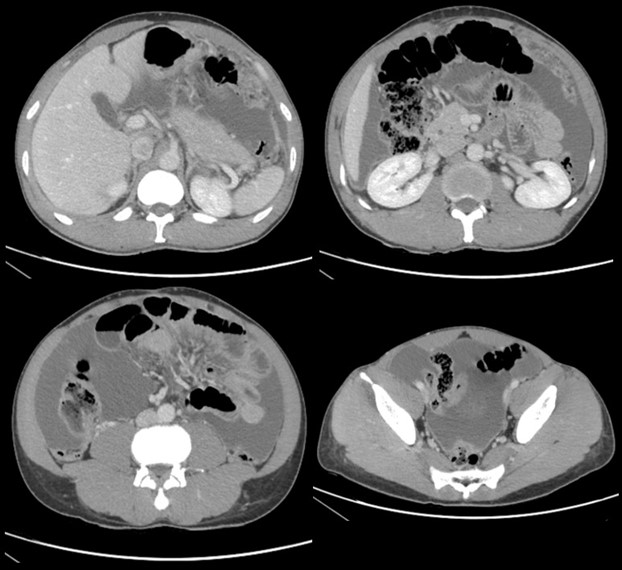

TAC abdominopélvico: abundante líquido libre intraperitoneal con signos de peritonitis y engrosamiento omental.